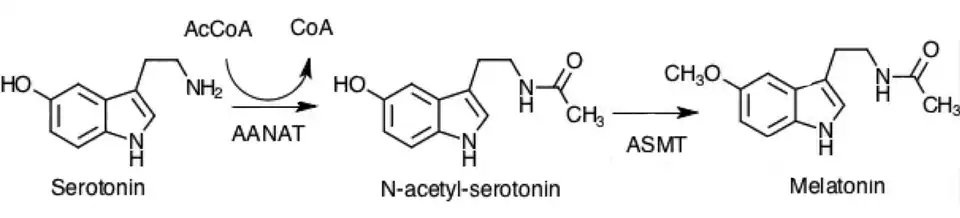

Синтез

Пинеалоциты синтезируют мелатонин, сначала преобразуя аминокислоту триптофан в серотонин. Затем серотонин ацетилируется ферментом AANAT и превращается в N-ацетилсеротонин . N-ацетилсеротонин превращается в мелатонин ферментом гидроксииндол O-метилтрансферазой (HIOMT), также известным как ацетилсеротонин O-метилтрансфераза (ASMT). Активность этих ферментов высока ночью и регулируется ранее обсуждавшимися механизмами, включающими норадреналин[1].

Регуляция синтеза мелатонина важна для основной функции мелатонина в циркадных ритмах . Основным молекулярным механизмом контроля, который существует для секреции мелатонина у позвоночных, является фермент AANAT (арилалкиламин N-ацетилтрансфераза). Экспрессия AANAT контролируется фактором транскрипции(выделения) pCREB. AANAT активируется через систему протеинкиназы A, в которой участвует циклический АМФ (цАМФ). Активация AANAT приводит к увеличению выработки мелатонина. Хотя существуют некоторые различия, характерные для определенных видов позвоночных, влияние цАМФ на AANAT и AANAT на синтез мелатонина остается довольно постоянным[9].